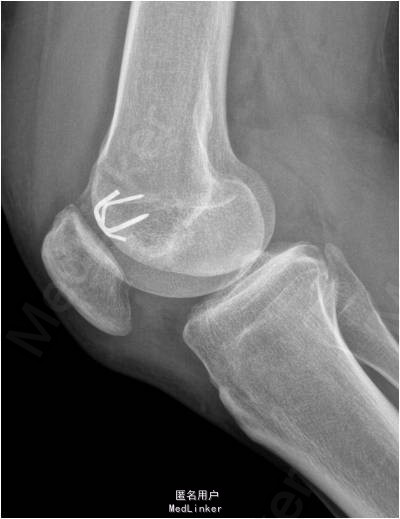

患者男,41岁,因“右膝关节镜术后3月余,依约返院”入院。患者3个月前因右膝髌股关节剥脱性骨软骨炎行“右膝关节门型钉固定术”,现患者依约返院行“门型钉取出术”。

诊断:1.右膝髌股关节剥脱性骨软骨炎术后;2.右膝关节半月板修补术后 行右膝关节镜检及门型钉取出术。术后第二天右膝关节可以开始负重。